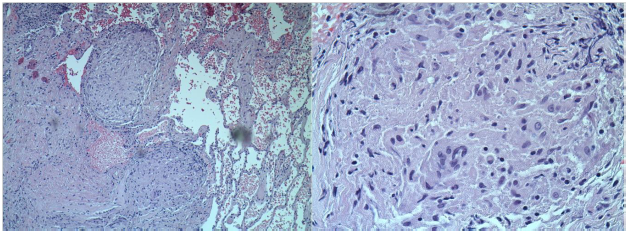

The patient was referred for a cardiac magnetic resonance imaging (MRI), which showed Left Ventricle (LV) dilation and severe LV dysfunction. The contrast study showed diffuse contrast late enhancement with patchy and confluent patterns characteristic of myocardial infiltrative process Figure 3.

Figure 3 Cardiac MRI (contrast enhanced) showing late enhancement and LV dysfunction.